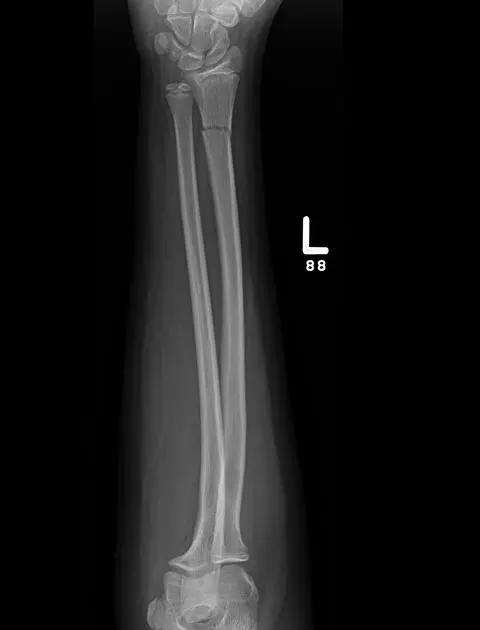

5. Maisonneuve 骨折

腓骨近端骨折伴内踝骨折及三角韧带断裂。

(来源:Radiopaedia)